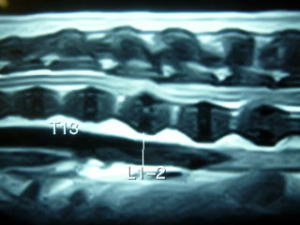

MRI検査を行いT13(胸椎の第13番目)−L1(腰椎の第1番目)間で、椎間板物質による脊髄神経の圧迫が見られたため手術を行いました。